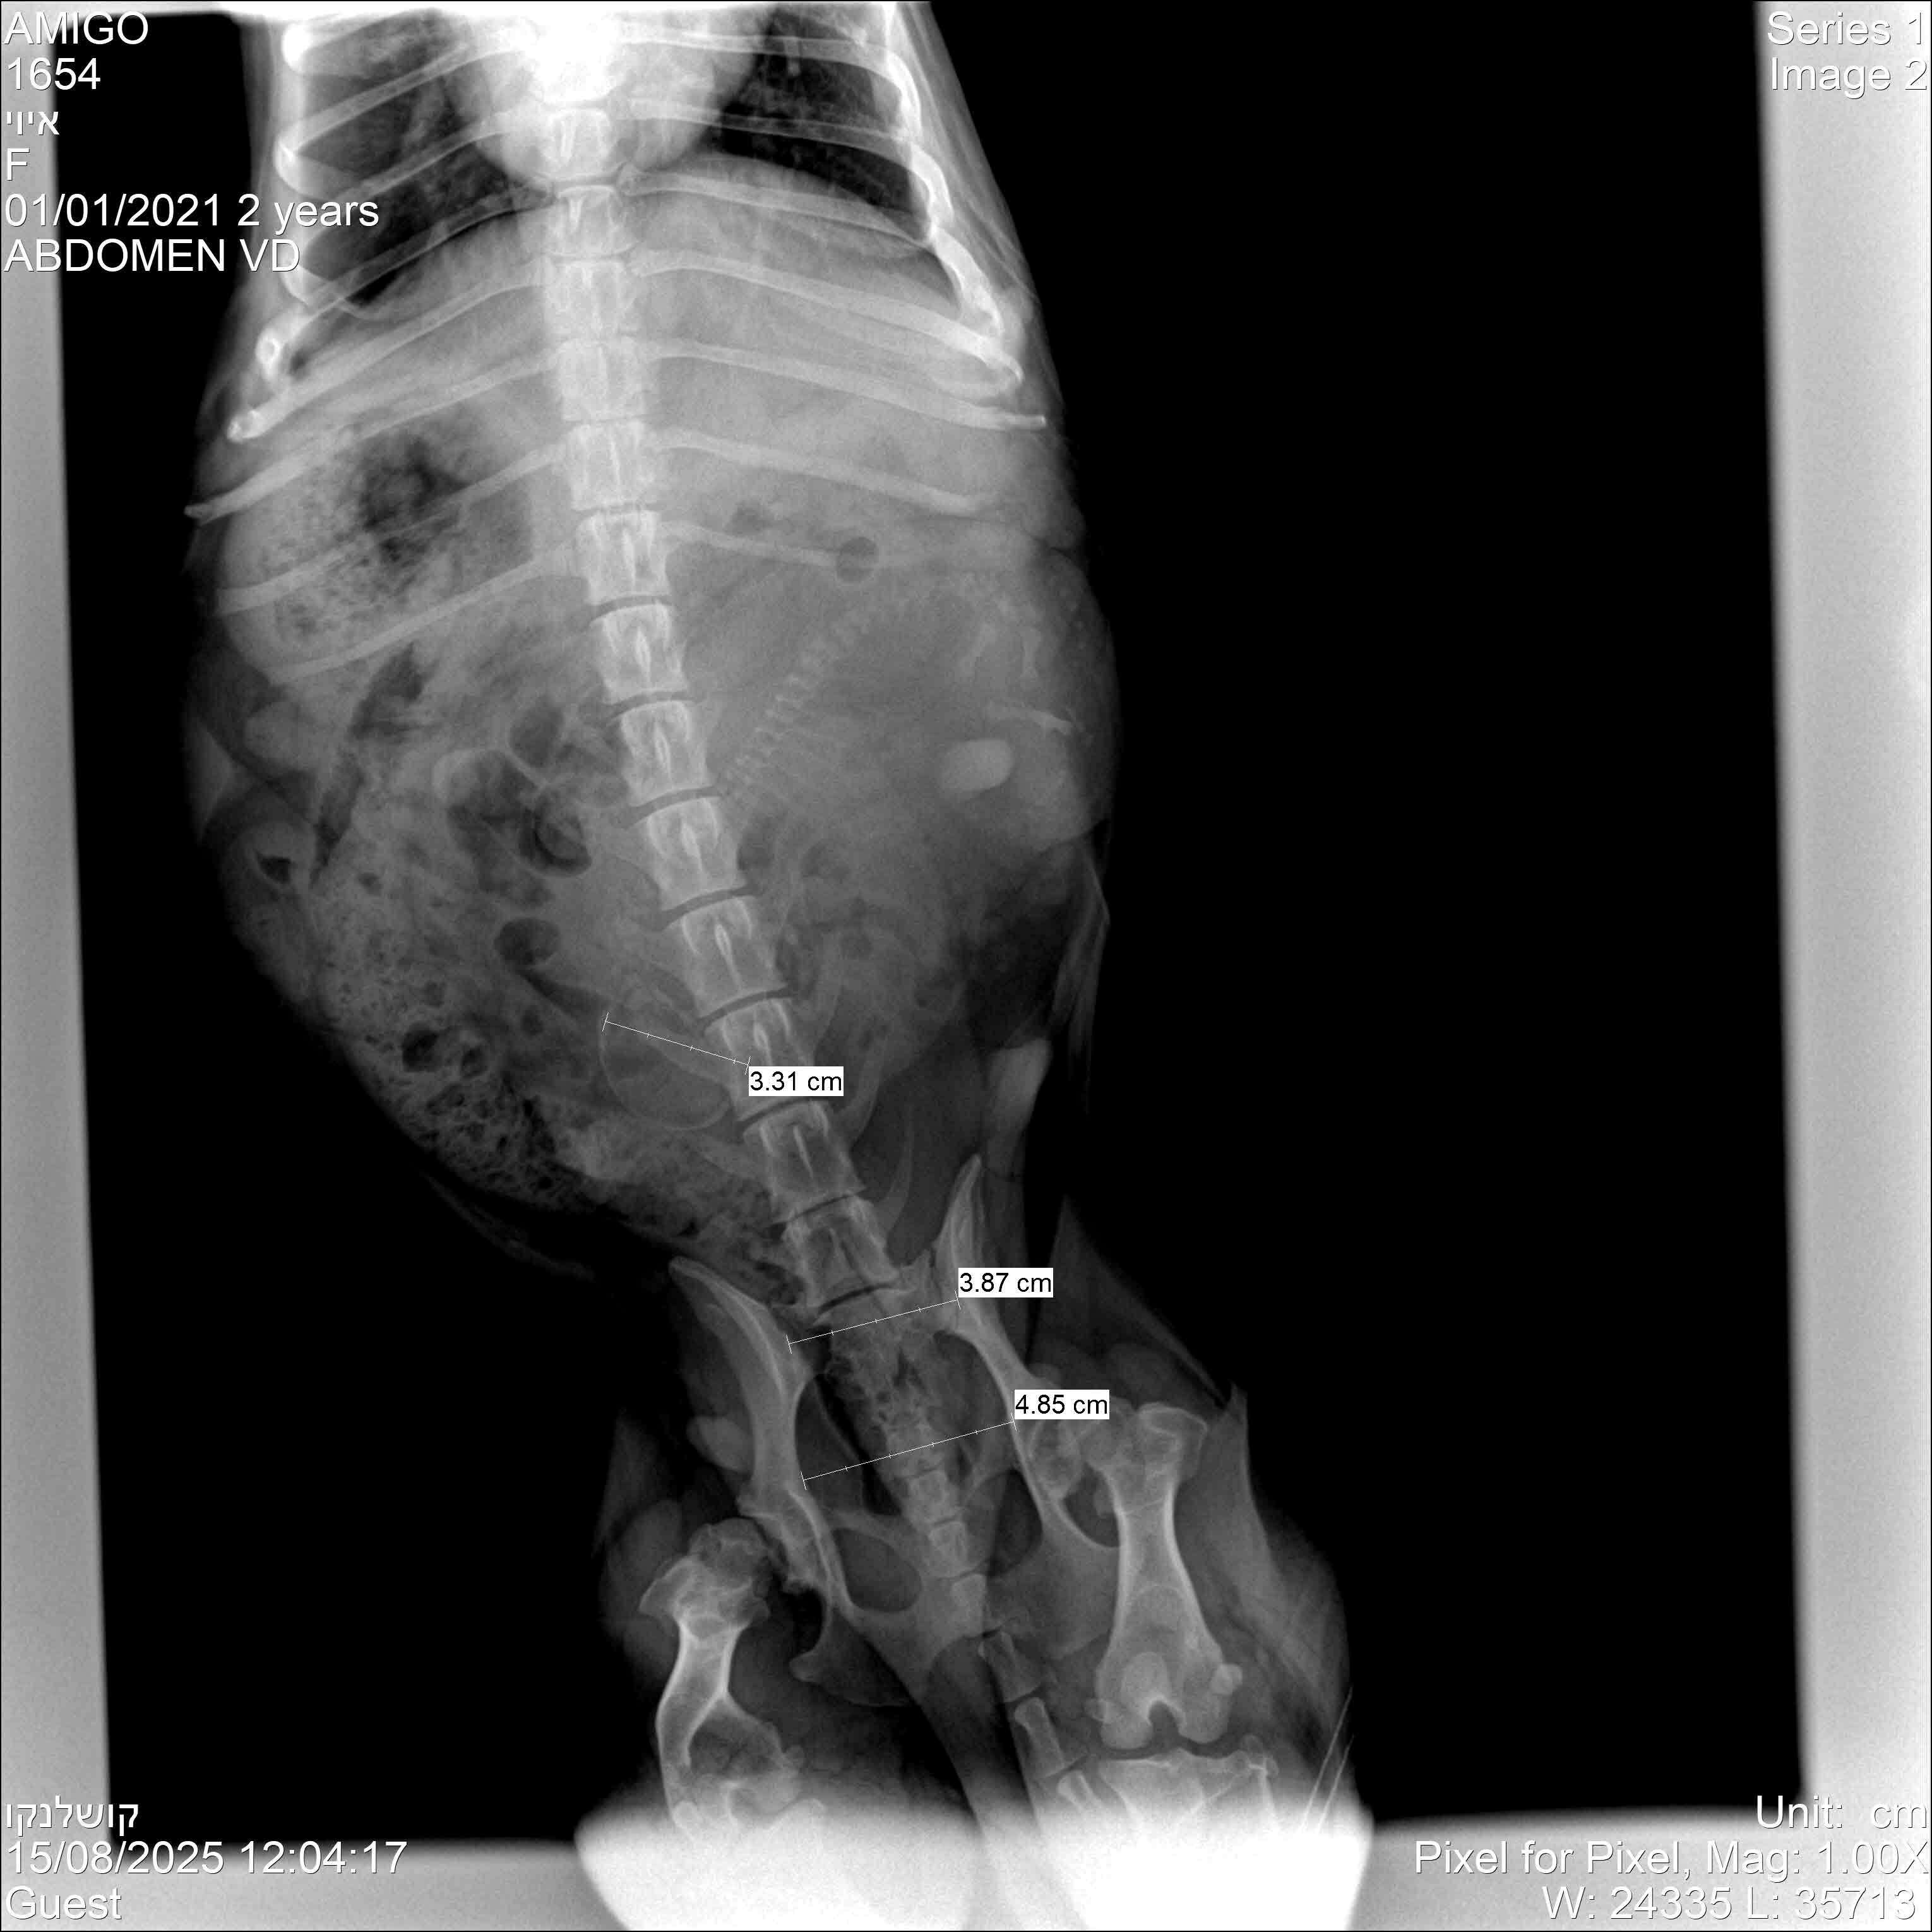

А 15 августа, на 55 день с вязки, мы поехали делать рентген - там можно посчитать щенков гораздо точнее (по головам или позвоночным столбам).

Ну вот... можете судить сами: